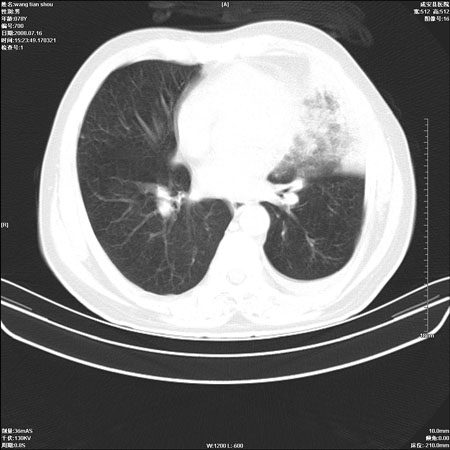

以下是引用qingjing在2008-7-16 19:55:00的发言:[br]1、左上肺不张并堵塞性炎症,建议支气管镜详查;[br]2、左侧胸腔少量积液。

以下是引用zsl6918在2008-7-17 8:09:00的发言:[br]肺炎胸膜炎可能性大,建议抗炎治疗后复查

以下是引用wzr在2008-7-16 20:26:00的发言:[br]左肺肺不张伴阻塞性肺炎!另:左侧胸腔少量积液。建议纤支镜检查!